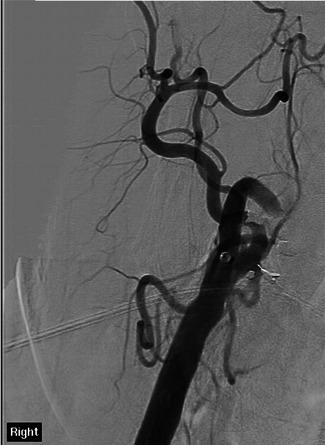

Of 5022 consecutive patients with AIS, 870 underwent EVT. Seven patients (0.8%) had EVT following cardiac surgery. Operations varied: two coronary artery bypass grafting (CABG), two transcatheter AVR, one redo surgical aortic valve replacement (AVR), one mitral valve repair and one patient with combined aortic and mitral valve replacements and CABG. Meantime postsurgery to stroke symptoms onset was 3 days (range 0-9 days). Median NIHSS was 26 (range 10-32). Five patients had middle cerebral artery occlusion and two internal carotid artery (n = 2). Median time between onset of symptoms and recanalization was 157 min (range 97-263). Two patients received Intra-arterial Thrombolysis. All patients survived and were discharged to another hospital (n = 3), home (n = 2), or rehabilitation facility (n = 2). Median 3-month mRS was 3 (range 0-6).

在 5022 例连续 AIS 患者中,870 例行 EVT。7 例(0.8%)在心脏手术后行 EVT。手术类型多样:2 例冠状动脉旁路移植术(CABG)、2 例经导管主动脉瓣置换术(AVR)、1 例再次外科主动脉瓣置换术(AVR)、1 例二尖瓣修复术和 1 例主动脉瓣和二尖瓣置换术联合 CABG。同时,术后至卒中症状发作时间为 3 天(范围 0-9 天)。NIHSS 中位数为 26(范围 10-32)。5 例患者大脑中动脉闭塞,2 例颈内动脉闭塞(n=2)。症状发作至再通的中位时间为 157 分钟(范围 97-263)。2 例患者接受了动脉内溶栓治疗。所有患者均存活并出院至另一家医院(n=3)、家中(n=2)或康复设施(n=2)。中位 3 个月 mRS 为 3(范围 0-6)。